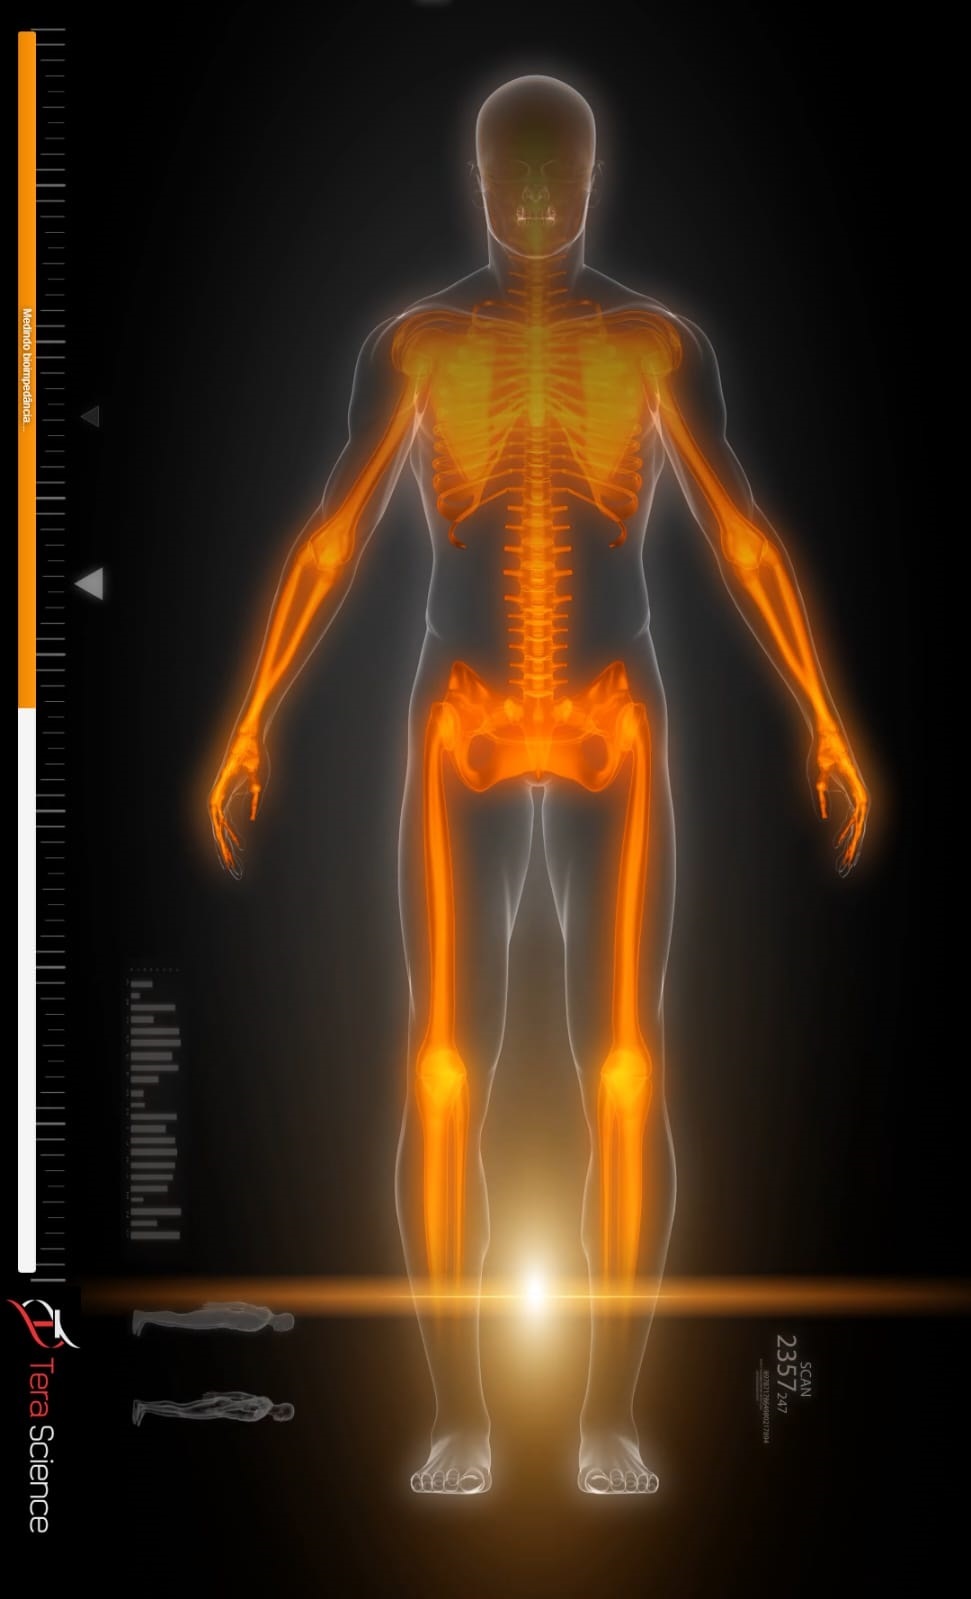

Com tecnologia tetrapolar multifrequencial, oferecemos um método moderno e altamente preciso de análise corporal.

Em apenas 60 segundos, quatro eletrodos posicionados na mão e no pé direitos realizam um mapeamento metabólico completo, fornecendo informações detalhadas sobre o funcionamento do seu corpo.

Ângulo de Fase: indicador essencial da vitalidade celular e de processos inflamatórios